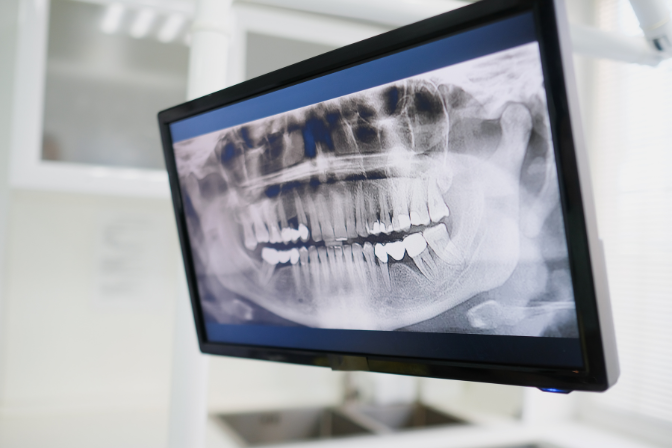

Our Maxillofacial Dentistry department offers a range of procedures, including orthognathic surgery for jaw misalignment, dental implant placement, and management of facial trauma such as fractures. We utilize advanced diagnostic tools like 3D imaging, CBCT scans, and digital planning software for precise treatment planning. Our team also provides cosmetic and reconstructive procedures, such as cleft lip and palate repair, and treatments for temporomandibular joint (TMJ) disorders. We emphasize minimally invasive techniques to reduce recovery time and enhance patient comfort.